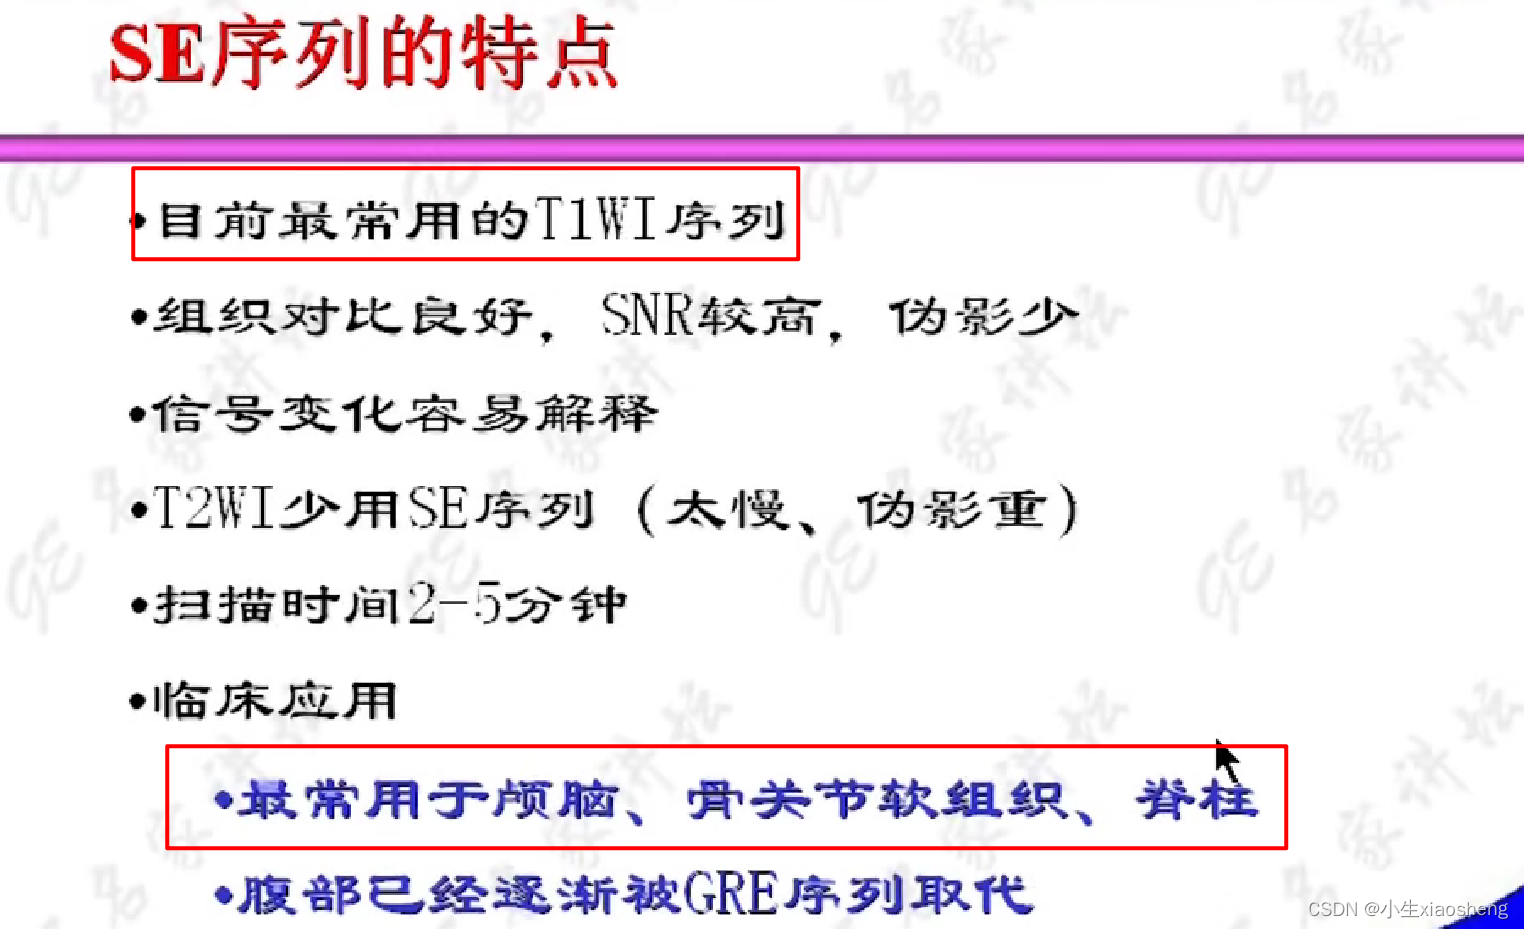

1.自旋回波序列SE

选择合适长的TE获得最好的T2对比:一般TE选择两种组织生物T2值附近可获得最好的T2对比。

选择合适短的TR获得最好的T1对比:一般TR选择两种组织生物T1值附近可获得最好的T1对比。